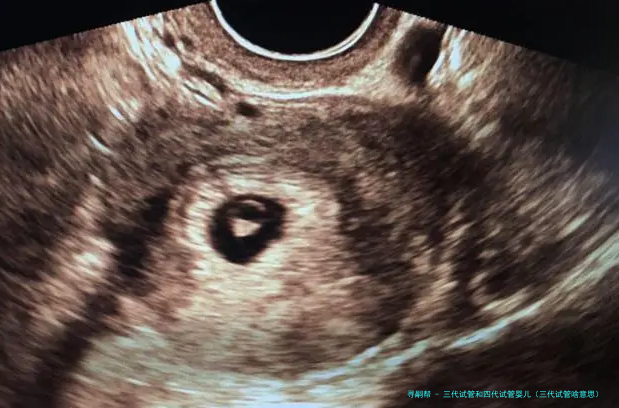

试管婴儿的医学术语称:胚胎转移技术-胚胎移植,其过程是女的一方先使用药物促排卵,再从卵巢内拿出卵子,男方拿出精子,在实验室将精子、卵子结合培育成胚胎,然后又将胚胎转至子宫腔内,令其着床、妊娠。

“试管婴儿”的完整名称叫做“试管受孕和胚胎移植术”(试管婴儿(IVF)-ET),是一种今世诊疗技术。原理是将卵子、精子分别拿出体外,在人工受控制条件下完成精卵结合,成活后再受精卵移植到母亲身内,着床发育。

试管婴儿道理 “试管婴儿”其实不是真正在试管里长大的婴儿,而是从卵巢内拿出若干个卵子,在实践室里使之们与男方的精子结合,形成胚胎,然后挪动转移胚胎到子宫内,让它位于妈妈的子宫内着床、妊娠。